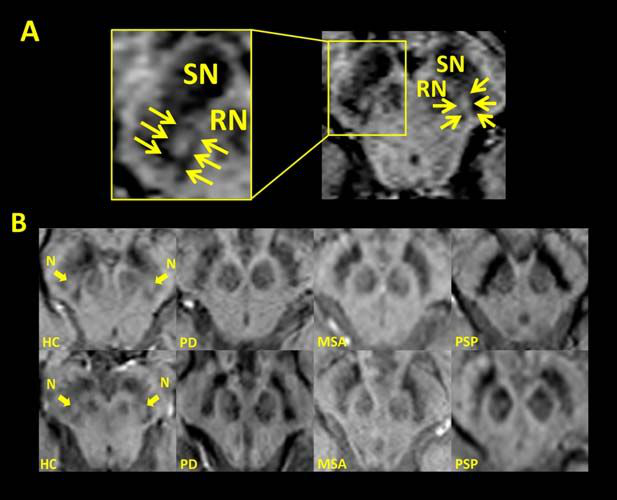

PD 的 MR 表現(xiàn):早期表現(xiàn)往往正常;晚期可出現(xiàn)黑質(zhì)致密部失去正常高信號,邊緣變?yōu)槟:?。黑質(zhì)正常燕尾形態(tài)縮小和喪失。

正常情況下燕尾征-SWI 的顯示:從上至下連續(xù) 1-5 層,黑質(zhì)(SN)出現(xiàn) 5 層,紅核(RN)出現(xiàn) 4 層,黑質(zhì)背外側(cè)部高信號一般位于位于黑質(zhì)的后 1/3,在紅核最后一層或消失的層面出現(xiàn)。

PD、MSA 和 PSP 出現(xiàn)燕尾征-SWI 高信號的消失

燕尾征-SWI 高信號的消失對于鑒別神經(jīng)退行性變和非退行性病變可能具有意義,但是對于鑒別帕金森病與帕金森綜合征還是缺乏準確性的。